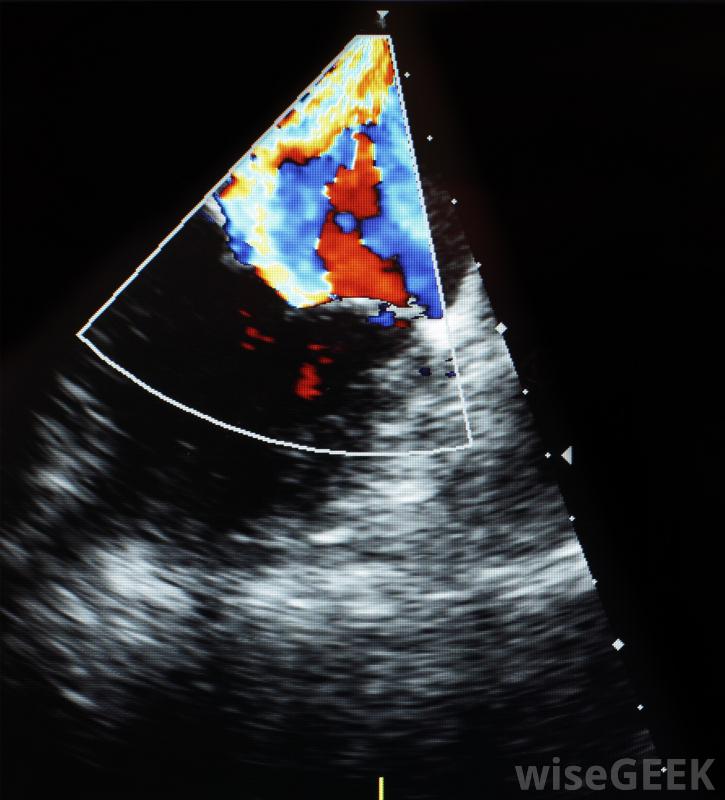

醫用多普勒設備使用高頻聲波監測內臟。

醫學領域使用數字多普勒來拯救生命。在這種情況下,電磁波被用來給醫生一個身體內部的視覺表現,而不切割皮膚。這些波可以產生二維或三維視圖指體內的器官或異物。妊娠超聲利用二維和三維多普勒給父母和產科醫生一張嬰兒的第一張照片。